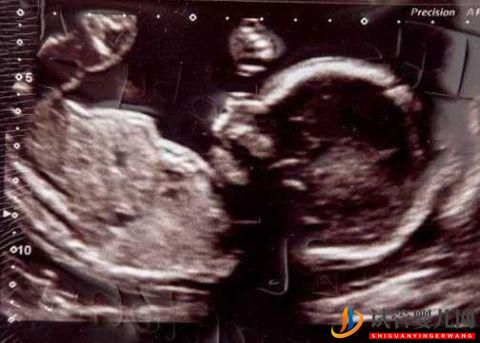

夫妇拒绝NHS(英国国家医疗服务体系)试管受精治疗,反而去借£10,000(约合9万元)的现金贷。但现在必须偿还£24,000(约合22万元)的现金。现年已经48岁的孕妈Carolyn,花了23年努力怀孕。下个月她终于要迎来自己的第一个宝宝。她和34岁的丈夫Michal表示,对这笔现金贷巨额贷款毫不后悔。

借了利率高达49.9%的现金贷,未来五年他们俩必须偿还£23,715的现金。作为NHS的管理者的Carolyn,找到了现金贷公司Amigo,给她资助了六轮试管受精费用。令她高兴的是,她怀孕了并将于下个月生下一个名叫Kayleigh的女儿。“我一点也不后悔。如果不是贷款,我现在都不会怀孕”